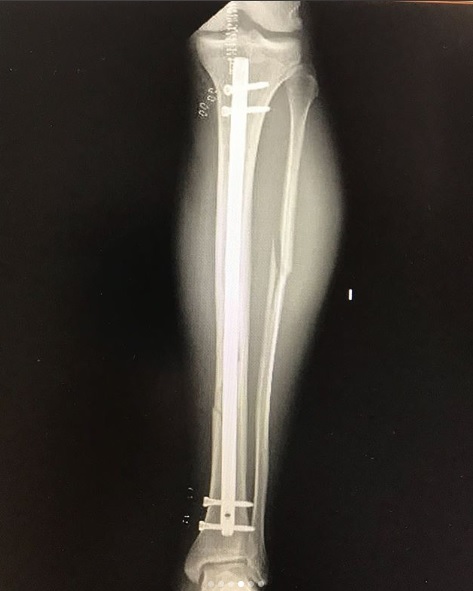

Luego de que su tabla se trabara, y su cuerpo diera un giro de 360°, el modelo argentino terminó con una rotura de tibia y peroné. “Creo que fue el peor dolor que he sentido”, reveló en su cuenta de Instagram.

Mediante su cuenta de Instagram, Ferres compartió con sus seguidores, capturas de las ecografías su pierna, donde se pueden apreciar las graves roturas que sufrió en dos huesos de su pierna izquierda.

Maxi Ferres| Instagram